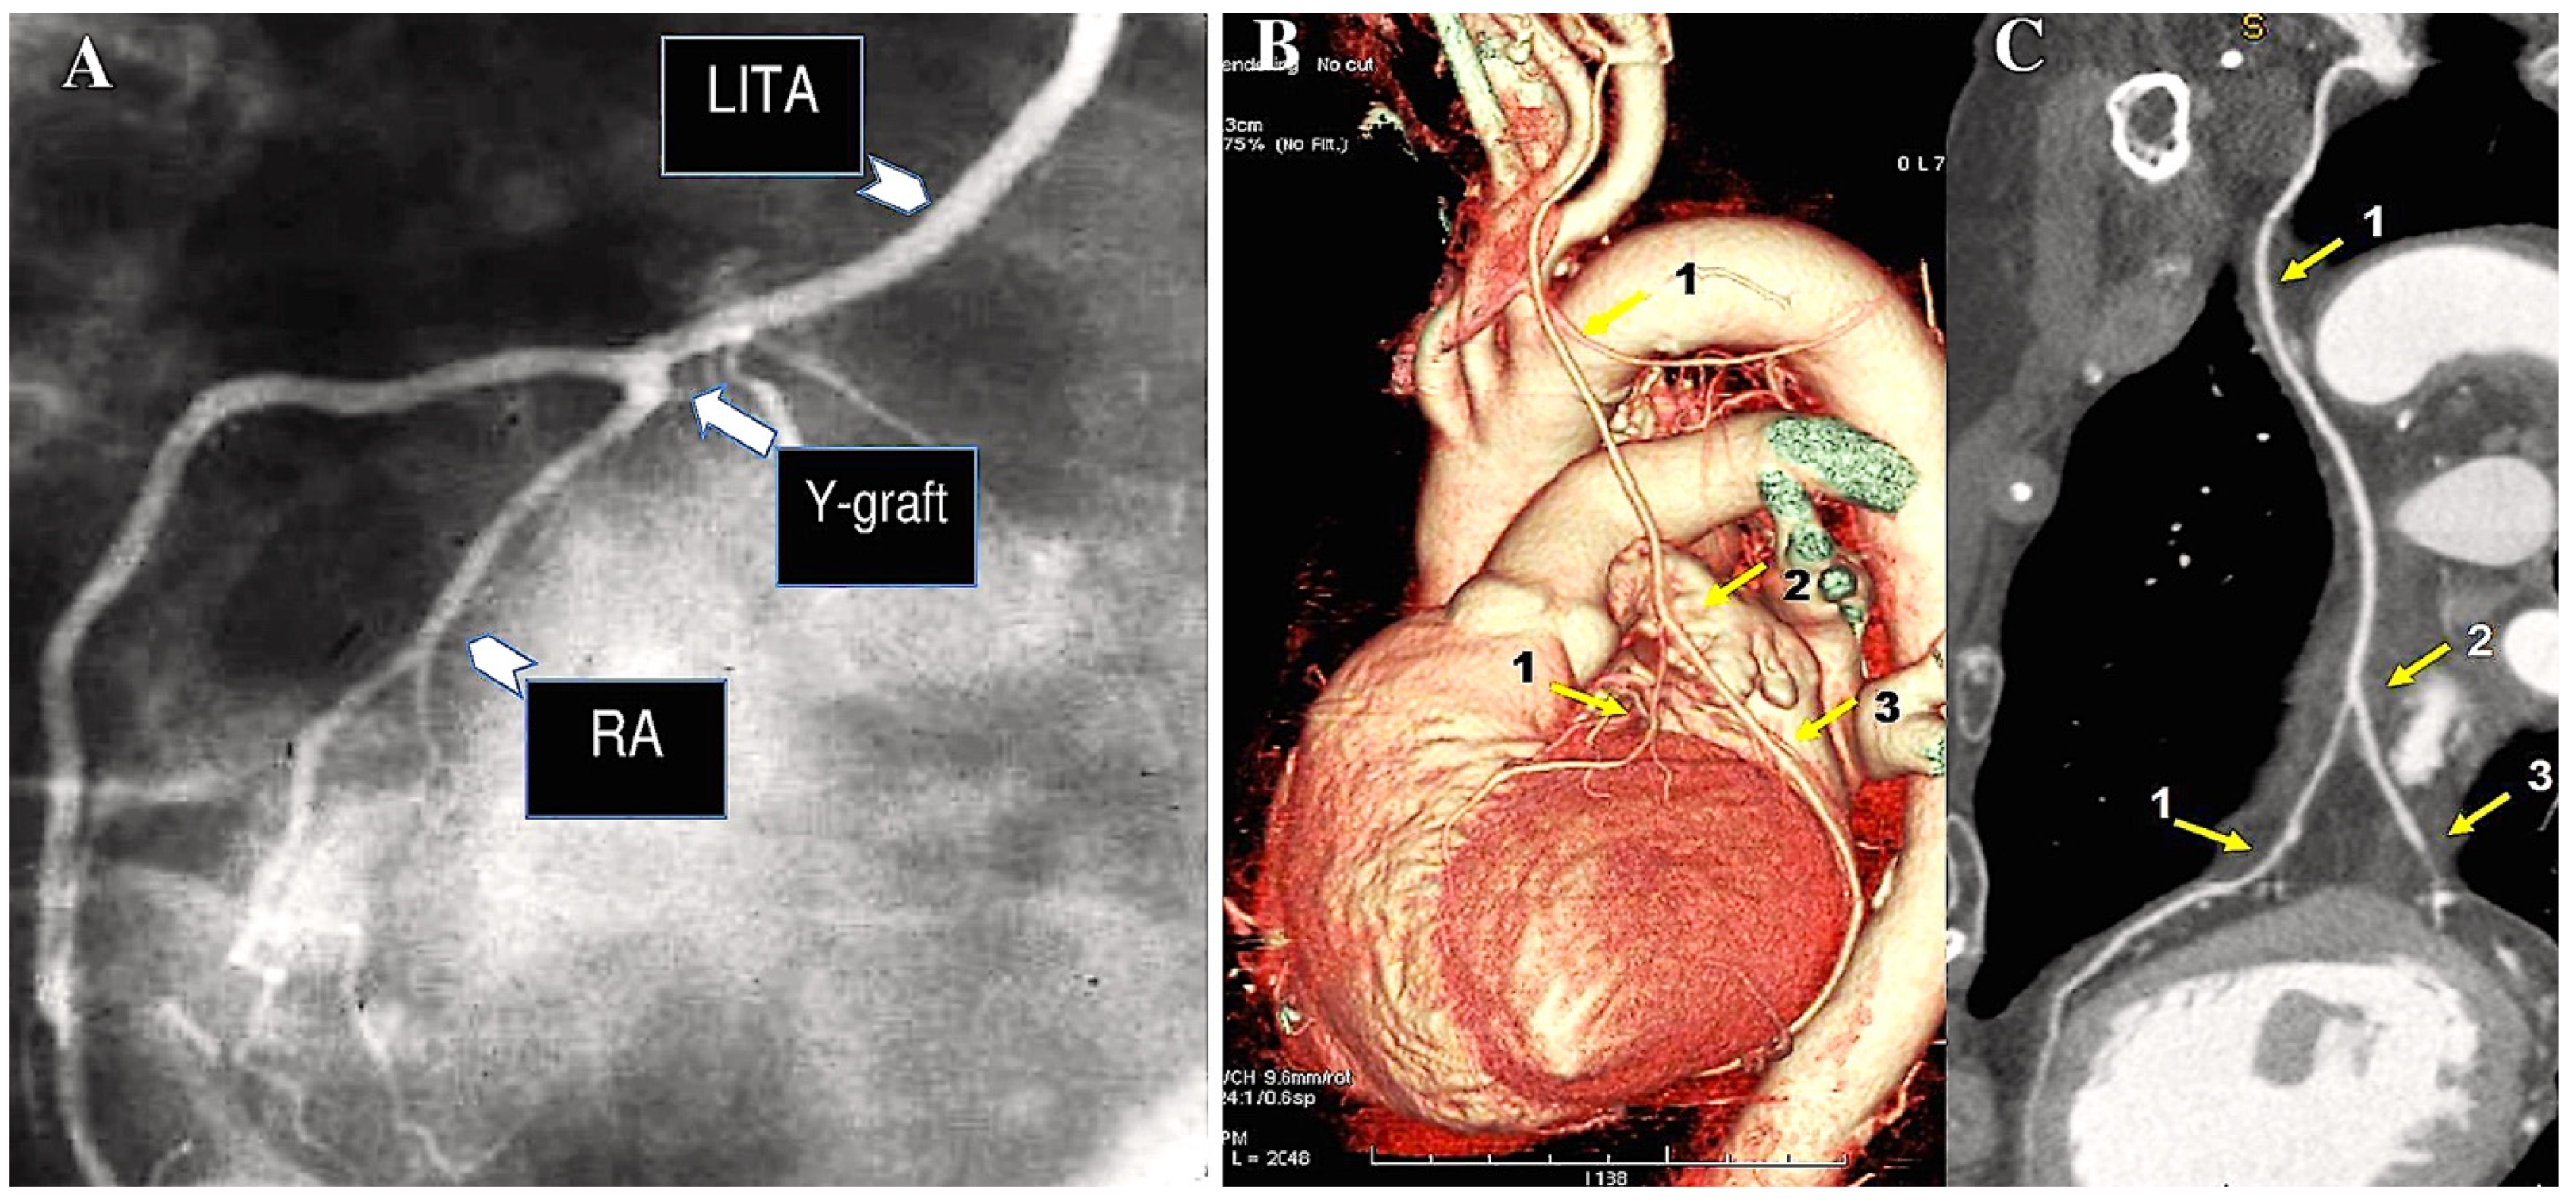

6. The Destiny of Radial Artery Grafts

Determinants of RA Patency